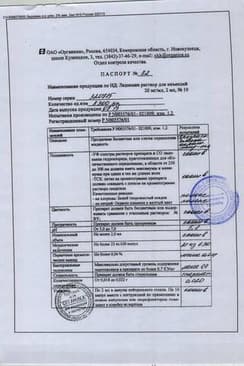

Лидокаин раствор для инъекций ампула 20 мг/ мл ампула/блистер 2 мл 10 шт

Состав препарата Лидокаин

Раствор для инъекций1 мл1 амп.

лидокаина гидрохлорид 20 мг 40 мг

2 мл - ампулы (10) - пачки картонные.